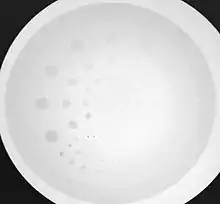

Let’s continue by considering two equally-sized small areas of a hypothetical digital image containing nine pixels. And let’s consider that the number of X-ray photons collected by each pixel is given by the numbers in Figure 6.16. We can estimate that for the area on the left, the average number of photons detected is 100, while that on the right, possibly as a result of lower attenuation, collects an average of 10,000 photons. The variation in the individual pixels within each area can be estimated statistically from the standard deviation of the number of detected photons. The standard deviation can be calculated from the square root of the mean when the photon number is assumed to follow a Poisson distribution as is the situation in radiography. The variation arises because of the random nature of X-ray emission that occurs within the anode of the X-ray tube and gives rise to what is called Quantum Noise.